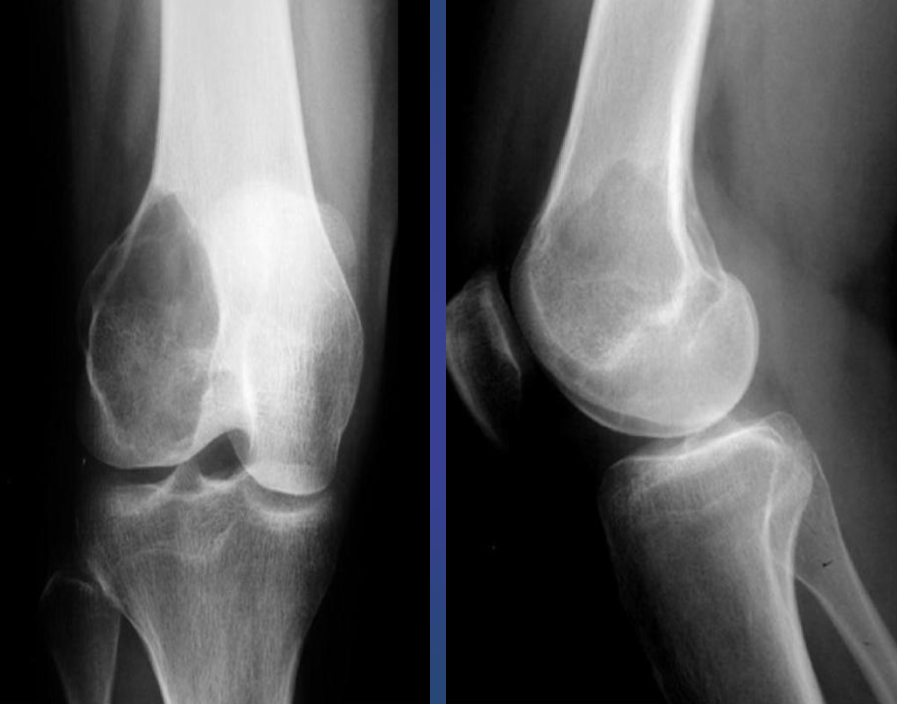

A. Give ONE radiological sign for an abnormal

wrist/knee.

B. What is the most likely diagnosis in the given image? Rickets

- Growth plate is widened

- Metaphysical margin is cupped and irregular

Imaging modality Lateral compartment osteoarthritis of the knee X-ray right knee (AP view)

Findings Osteophytes - bone spurs // Subchondral Sclerosis

Diagnosis Osteoarthritis